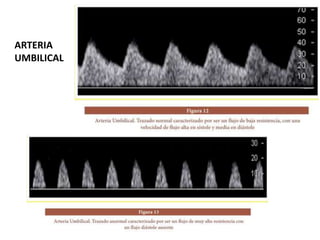

FLUJOMETRÍA DOPPLER

• Evaluación no invasiva del estado hemodinámico

fetal.

• Arterias umbilicales (función uteroplacentaria y la

circulación fetoplacentaria).

• Vasos fetales (estado fetal).

• Indicaciones

– Restricciones crónicas de la función placentaria (HT, LES, sd

antifosfolípido, diabetes pregestacional, vasculopatías, etc).

Insuficiencia placentaria

Incremento de

la resistencia

vascular en la

arteria

umbilical.

Redistribución

hemodinámica,

con

disminución de

vascular.

cerebro, corazón y gls

adrenales. Hipoperfusión en

riñones, intestino y

extremidades.

Oligoamnios

por

hipoperfusión